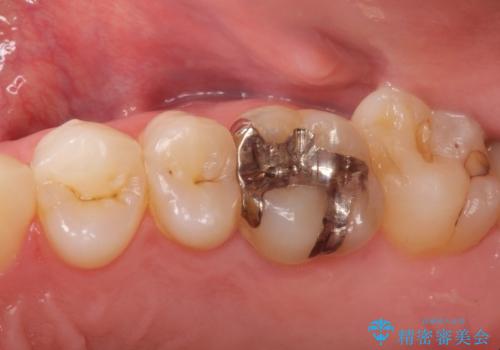

メタルフリー セラミックインレー

- メタルフリーの治療を希望されて来院されました。

セラミックインレーの治療を2回の来院で終了しております

e-max プレスインレーにて修復治療を行っているため適合性及び審美性の高い治療を行うことができます